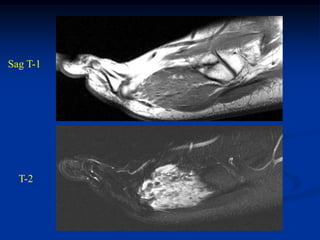

Case #1209

17 year male with

hemangioma in

quadriceps muscle

Axial T-2 MRI

Case #1209 17 yearmale with hemangioma in quadriceps muscle Axial T-2 MRI